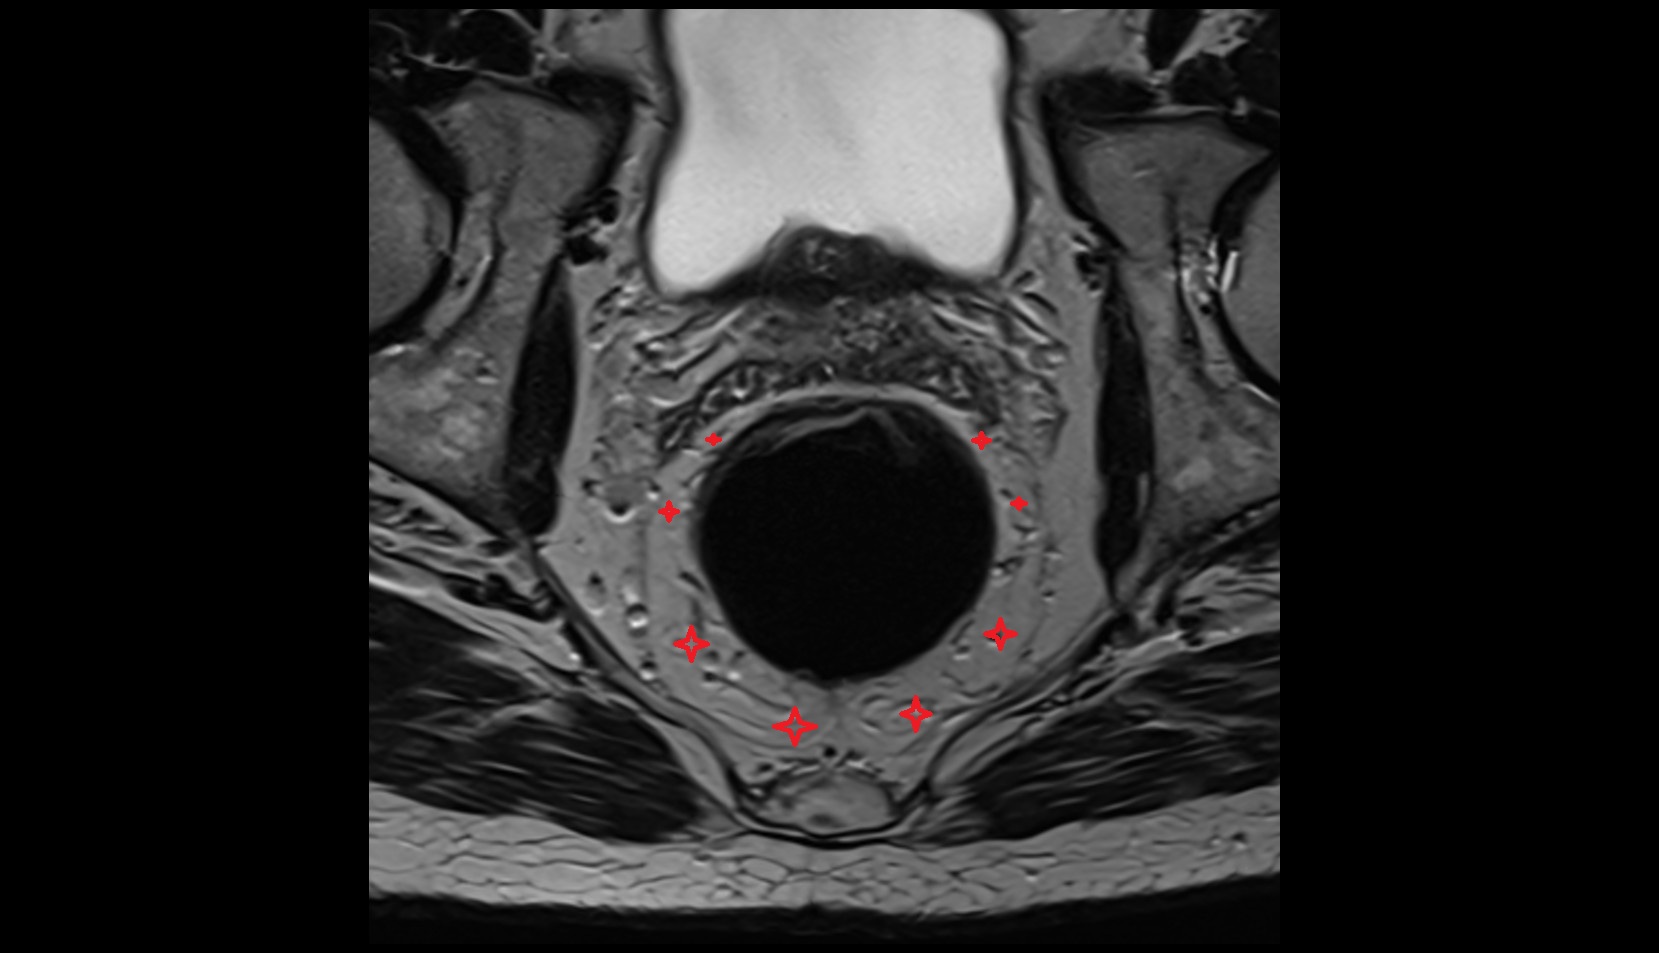

- Peripheral zone of prostate

- Anterior Fibromuscular Stroma of prostate

- Central zone of prostate

- Transitional zone of prostate

- Rectoprostatic fascia (Denonvilliers' fascia)